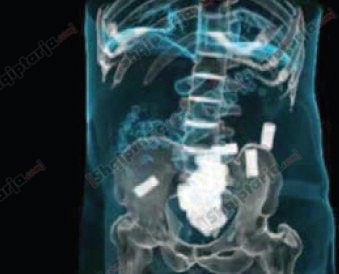

DROGË NË STOMAK

Në Shqipëria janë dy raste të trafikut të tillë, kur transportuesi e kishte futur lëndën narkotike në stomak. Trafik i tillë bëhet për lëndë narkotike të forta si, heroina apo kokaina. Në këto raste, personat i gëlltisin topat e lëndës narkotike që janë mbështjellë me material që nuk e kalon lagështirën.